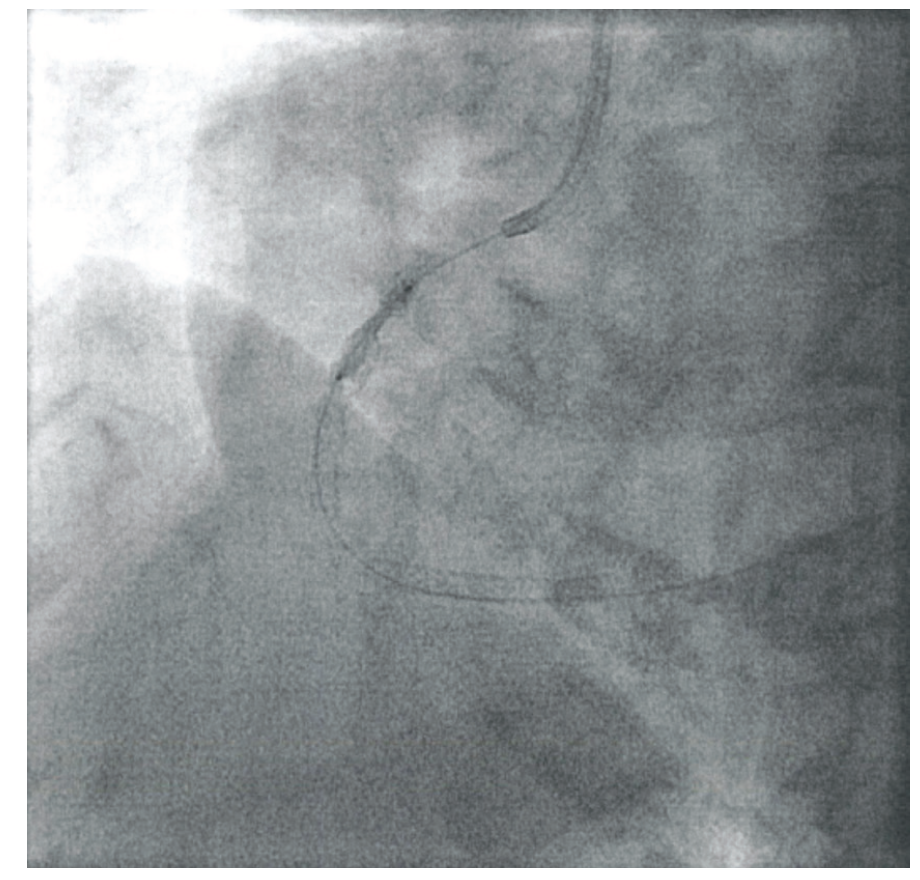

The patient was brought to the lab and plans were made to perform intravascular lithotripsy. After a NC balloon could not expand (Figure 2), a 3.0 mm Shockwave lithotripsy balloon was advanced and positioned inside the stent (Figure 3). Four pulses of IVL were given. After the 4th pulse, the lithotripsy balloon waist disappeared (Figure 4). The lesion was then expanded without any difficulty using a standard 4.0 mm NC balloon. Intravascular ultrasound showed the fractures in the walls of the artery after Shockwave IVL (Figures 5-6). An excellent angiographic result (Figure 7) was obtained and the patient was discharged home the same day.